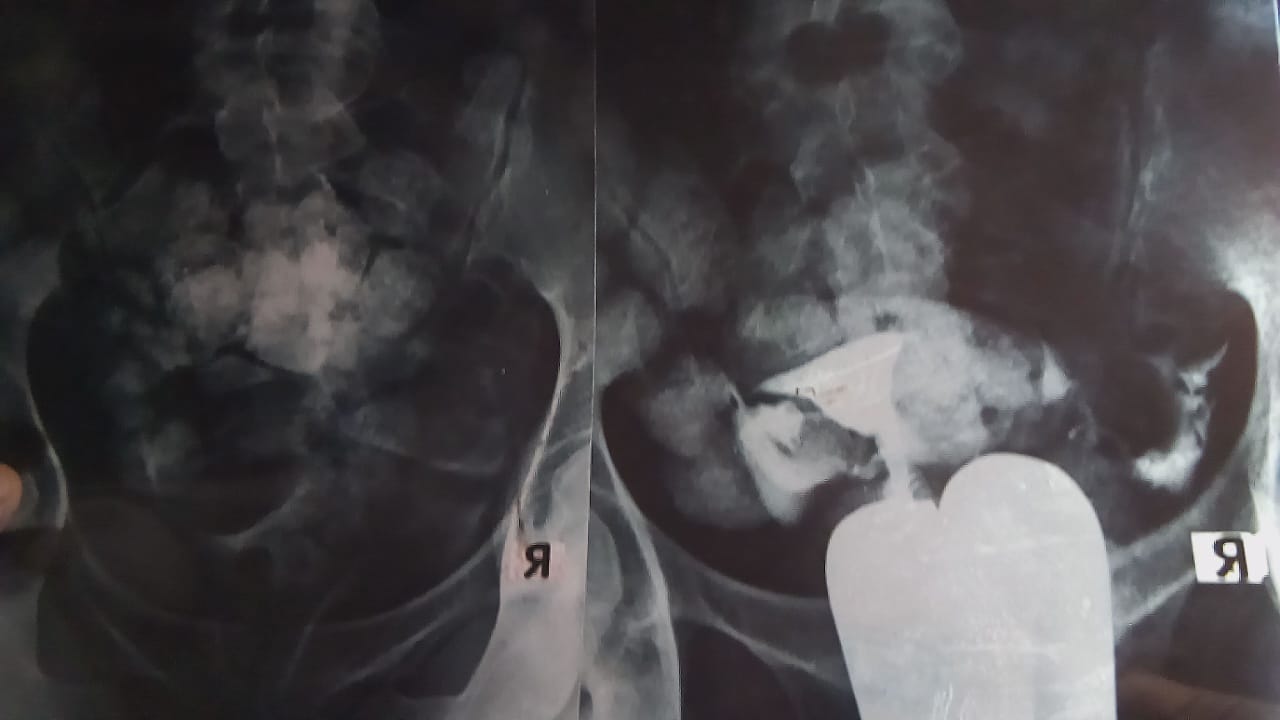

بدأت رحلة علاج الزوجة بعد مرور 7 سنوات من الزواج دون حدوث الحمل إلا مرة واحدة باءت بالفشل وانتهت بإجراء عملية تفريغ لإحشائها من نجلها الأول حرصاً على حياتها ، وعلى إثرها بدأ الزوجين بالتوجه إلى أكثر من طبيب متخصص واستشارى لإجراء التحاليل الطبية والأشعة المقطعية فى محاولة لعلاج الضرر وإتاحة الفرصة من جديد ، إلا أن جميع محاولاتهم جاءت بالسلب ، وخاصة بعد خضوع الزوجة لجراحتين كانتا لتوسيع أنابيب المبايض وإزالة الإلتصاقات الموجودة بالرحم

تقول منى حربى إمام يونس ٣٢ عاما ، من أبناء قرية تنيدة التابعة لمركز بلاط بمحافظة الوادى الجديد فى تصريح خاص لبوابة الجمهورية أون لاين، من أصعب اللحظات التى مرت بها ليلة التفريغ وهى جراحة اضطرارية خضعت لها بعد موت الجنين داخل احشائها بعد أيام من الحمل وخمس سنوات من الزواج كانت فى عام٢٠١٧م، مشيرة إلى أن الأمر لم يدم طويلا، وخاصة أنها لا تزال فى ريعان شبابها بعد مرور ٧ سنوات فقط من زواجها ، حيث بدأت رحلة البحث عن افضل أساليب العلاج لتفادى حدوث الأمر مرة ثانية ، فسافرت إلى محافظة أسيوط وأجرت جراحة لتوسيع أنابيب المبايض وإزالة كيس من الدم الفاسد بعد اكتشاف إصابتها بمرض بطانة الرحمية المهاجرة ، ثم انتقلت إلى محافظة القاهرة وخضعت لجراحة أخرى بعد إجراء التحاليل الطبية والأشعة لتفادى حدوث الإلتصاقات المتسببة فى منع فرص الحمل.